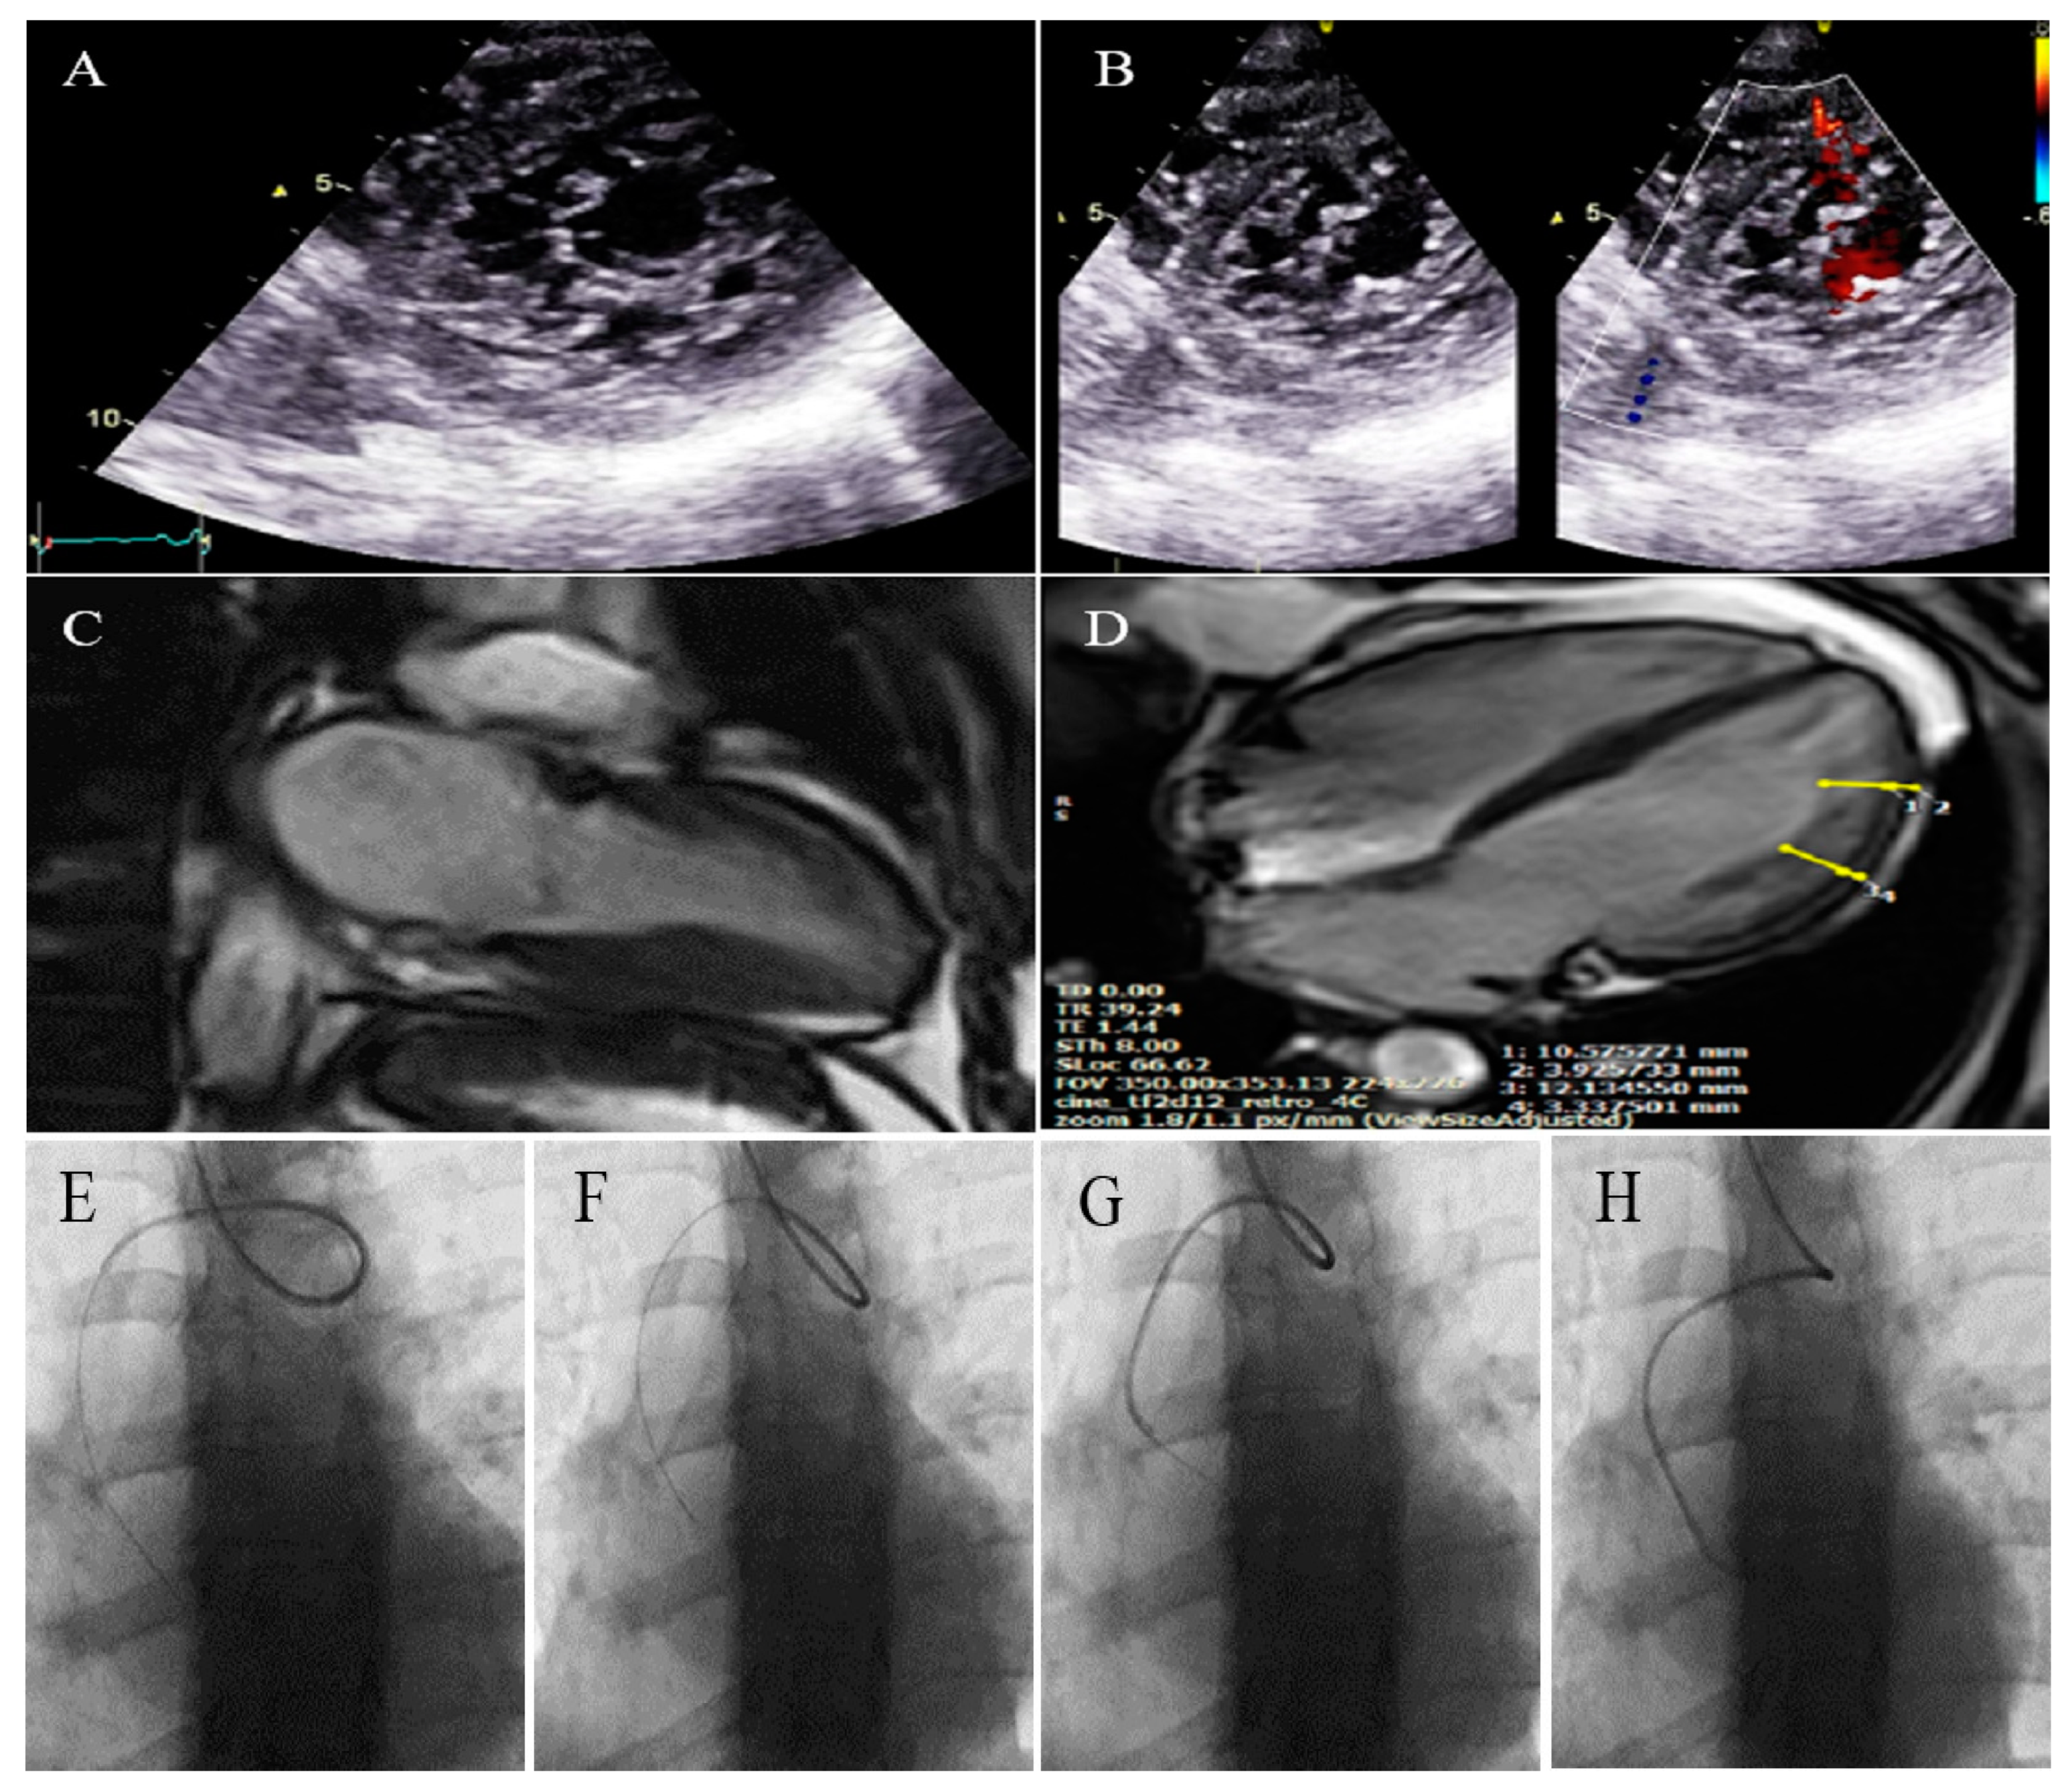

2.2. Case #2. NCLV, Patent Foramen Ovale (PFO), and Fast-Growing Aortic Aneurysm

| 2 | M | 56 | Progressive dyspnea | − | NCLV, LVEF = 16%, Global hypokinesia | Hypoplasia of ascending and arch of aorta plus dilated main pulmonary artery | + | − | Scheduled for a valve-sparing aortic root replacement surgery + post-op carvedilol 6.25 mg TID, furosemide 40 mg daily plus spironolactone 25 mg daily | Doing well |